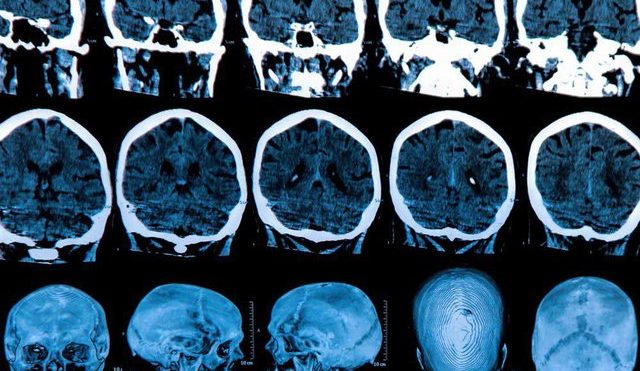

توالی‌های تکراری RNA های خاموشگر یافت شده در آسیب شناسی هانتیگتون بسیار شبیه به ملکول‌های RNAهای خاموشگر کشف شده در مطالعه پیشین تیم بودند. بنابراین گام بعدی آزمایش این بود که آیا این ملکول‌های خاص هنگامی که از طریق نانوذرات به  بدن موش‌ها منتقل شدند، واقعا برای کشتن سلول‌های سرطانی کار می کردند یا خیر. نتیجه باورنکردنی بود، رشد تومور به طور قابل توجهی در انواع مختلف سلول‌های سرطانی، از جمله سرطان تخمدان، پستان، پروستات، کبد، مغز، ریه، پوست و سلول‌های سرطانی روده بزرگ، کاهش یافت.